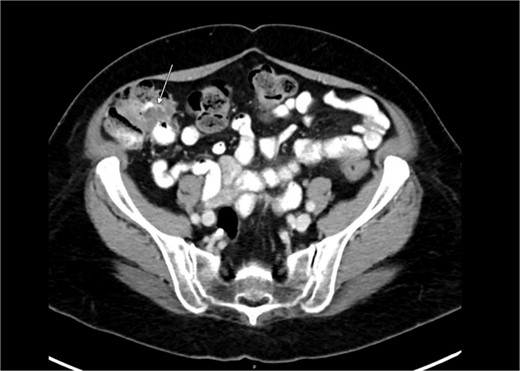

Preoperative abdominal computed tomography revealed a mass in the ascending colon (Fig. 1) and multiple nonspecific cystic lesions in the peritoneal cavity involving the abdomen and pelvis (Fig. 2). Normally, carcinomatosis would be suspected in a patient with mucinous adenocarcinoma of the colon. However, the radiographic findings were not definitive for carcinomatosis, and the history of abdominal ‘cysts’ 20 years previously further confused the situation. The differential at the time included malignant carcinomatosis, benign endometriotic cysts, and cystic peritoneal reaction to previously placed intraperitoneal hernia mesh. Carcinoembryonic antigen measured 0.8 ng/mL.

Computed tomography abdomen/pelvis—arrow indicates ascending colon mass.